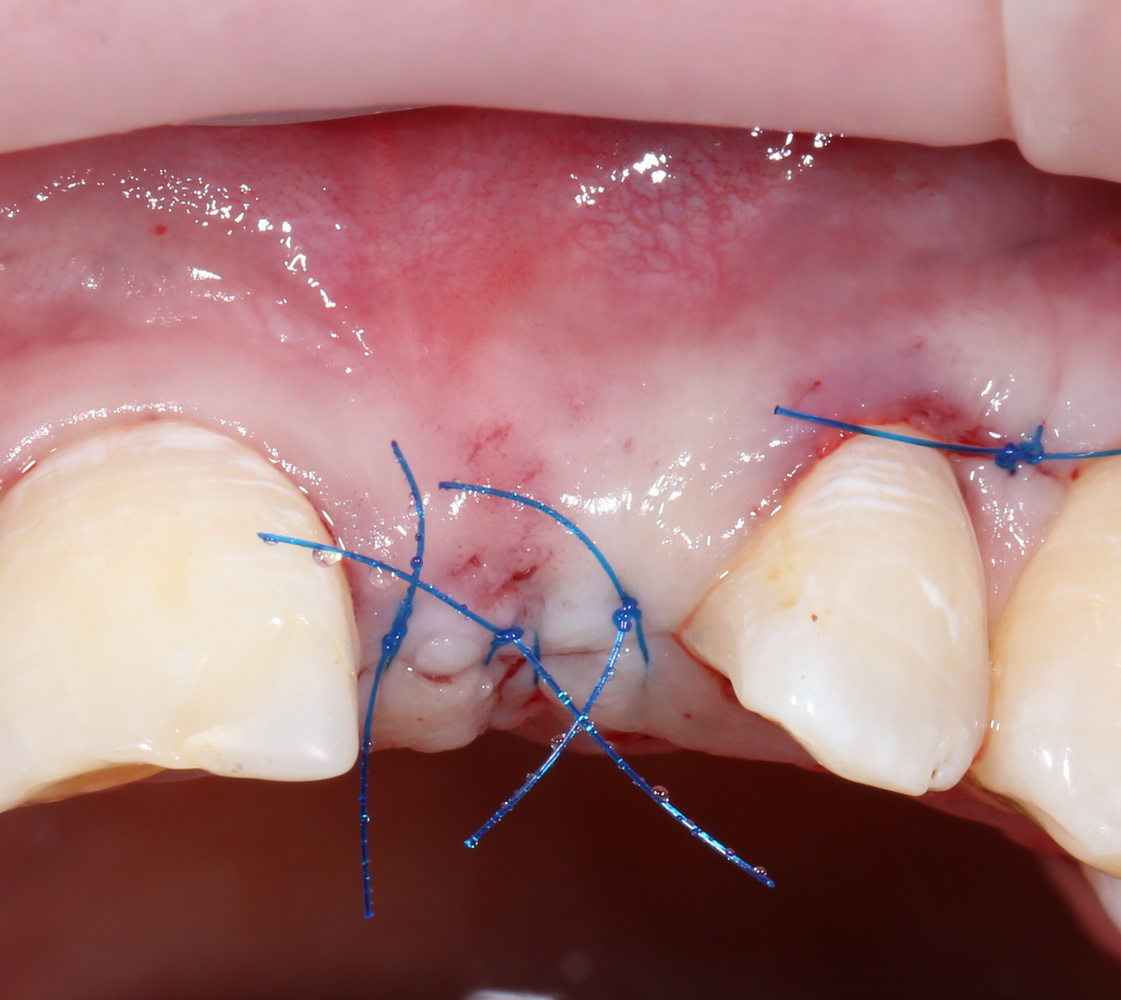

ну и, швы:

Друзья, он очень простой. Это швы. От качества швов зависит очень и очень многое.

Поэтому забываем викрил и другие плетеные материалы. Только нерезорбируемая мононить (Prolene, Resoprene и т. д.), только хардкор.